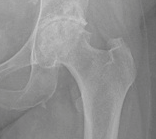

Che cos’è l’artrosi dell’anca

L’artrosi dell’anca è l’evoluzione di una condropatia non trattata: con il trascorrere del tempo la mancanza della cartilagine porta ad un’usura dell’articolazione con conseguente diminuzione dei movimenti e alla comparsa del dolore ogni volta che il paziente sta in piedi o cammina.

La forma di una anca artrosica è completamente diversa da quella normale: è come un ingranaggio danneggiato e, come in ogni “macchina”, se un meccanismo non si può aggiustare, va sostituito con un pezzo di ricambio.